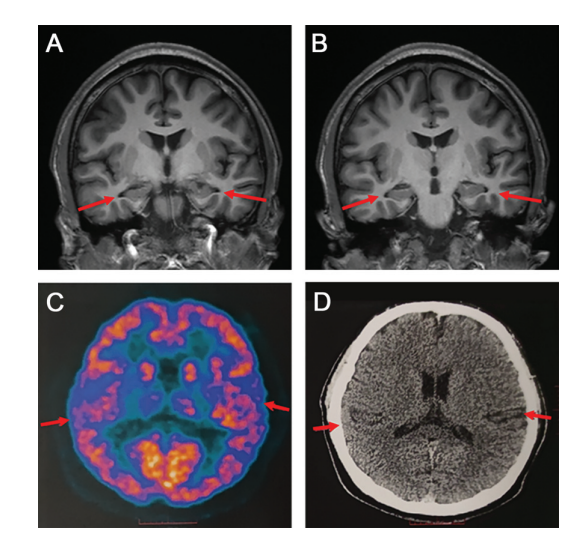

根据研究小组提供的资料显示,该患者在就诊前两年开始出现在学习时注意力难以集中,一年后,短期记忆丧失明显,无法回想起前一天发生的事或个人物品的存放位置,阅读困难,反应缓慢。

随着病程进展,记忆力进一步下降,经常丢失个人物品,记不清自己是否吃过饭,难以完成学习内容和老师布置的作业。由于记忆下降严重,他的学习成绩从之前的中等以上水平下滑到班内末位,无法完成学业,不得不从高中退学。